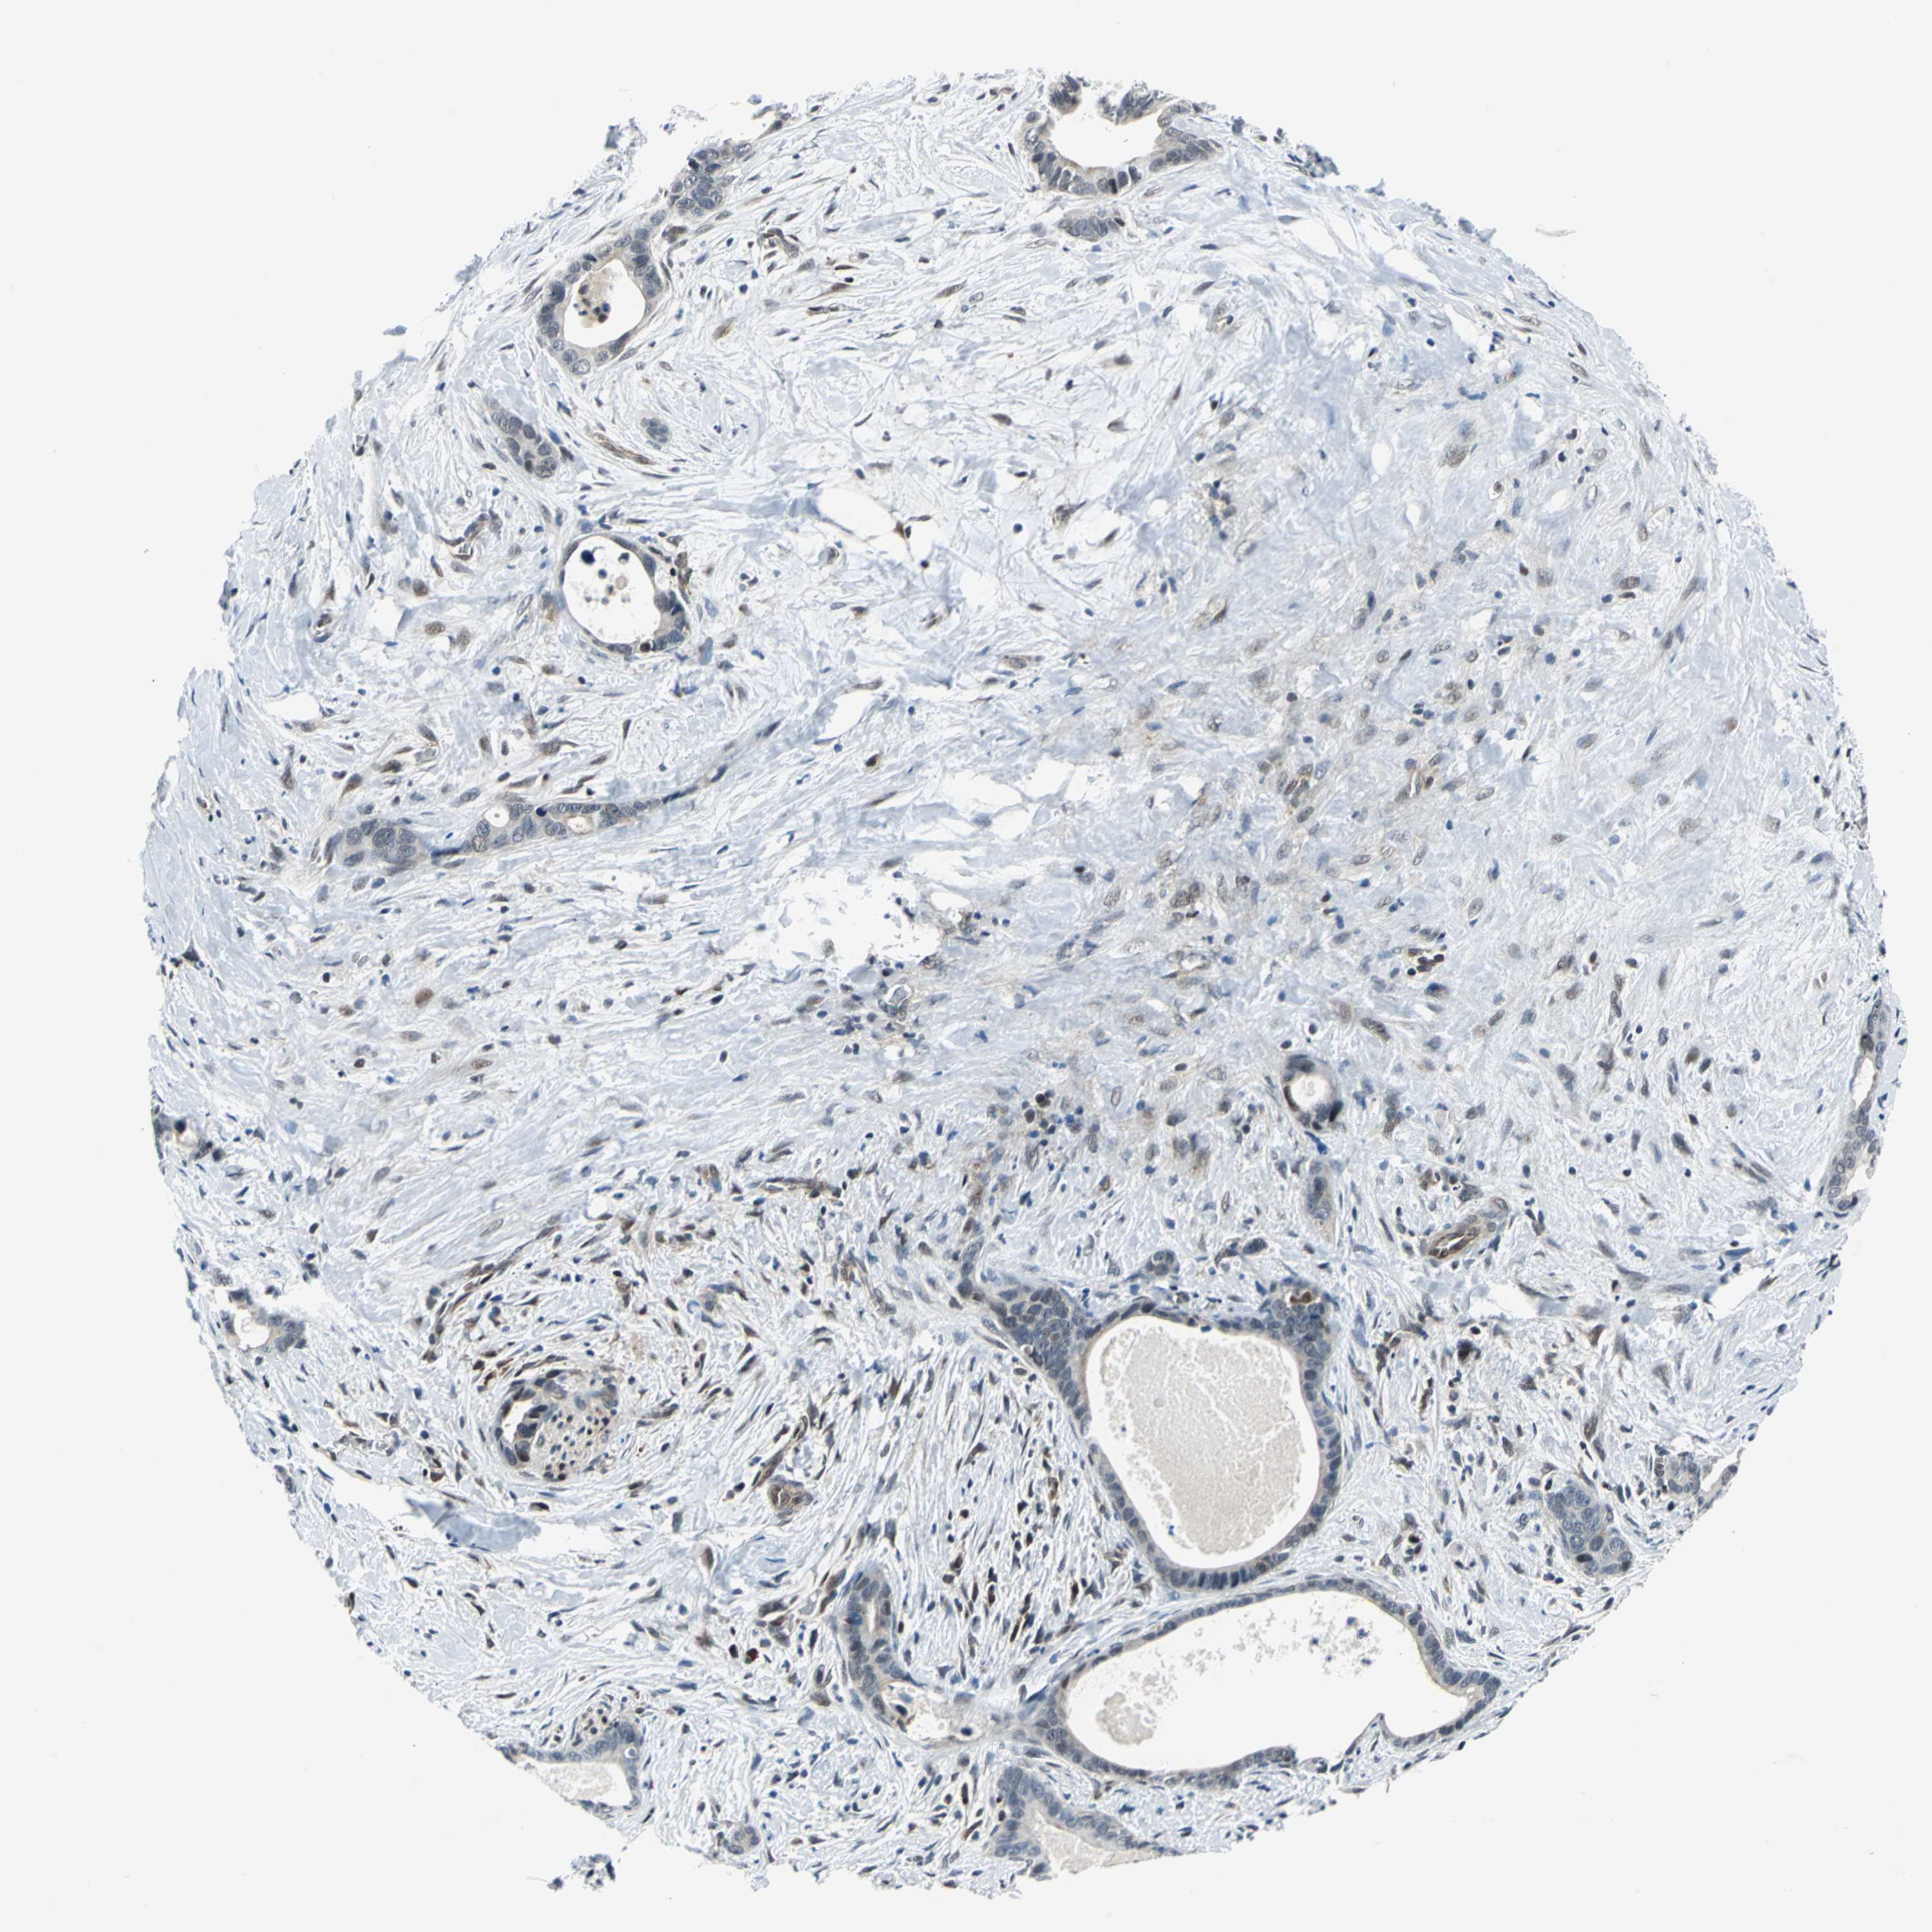

LIVER CANCER - Protein expressioni

A mouse-over function shows sample information and annotation data. Click on an image to view it in a full screen mode. Samples can be filtered based on level of antibody staining by selecting one or several of the following categories: high, medium, low and not detected. The assay and annotation is described here.

Note that samples used for immunohistochemistry by the Human Protein Atlas do not correspond to samples in the TCGA dataset.

Antibody stainingi

Antibody staining in the annotated cell types in the current human tissue is reported as not detected, low, medium, or high, based on conventional immunohistochemistry profiling in selected tissues. This score is based on the combination of the staining intensity and fraction of stained cells.

Each image is clickable and will lead to virtual microscopy that enables deeper exploration of all samples and also displays staining intensity scores, fraction scores and subcellular localization as well as patient and tissue information for each sample.

Antibody HPA005891

Staining

High

Medium

Low

Not detected

Intensity

Strong

Moderate

Weak

Negative

Quantity

>75%

75%-25%

<25%

None

Location

Nuclear

Cytoplasmic/membranous

Cytoplasmic/membranous,nuclear

Cholangiocarcinoma

Carcinoma, Hepatocellular, NOS